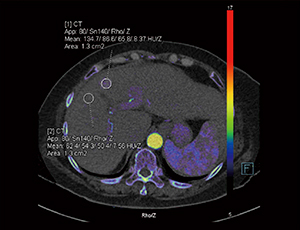

Dual Energyイメージングは,異なる2種類のエネルギーデータを取得・解析することをベースにした技術であり,画像コントラストの向上や物質の組成情報を特定することができる。取得した2種類のエネルギーデータは,Dual Energyイメージングの解析が可能な画像診断支援システム「syngo.via」に送信され,非剛体による自動位置合わせが行われた後,各種アプリケーションによる解析が行われる。40〜190keVの範囲で任意の仮想単色X線エネルギー画像を作成する“syngo.CT DE Monoenergetic Plus”では,金属アーチファクトの低減に加え,画像コントラストの最適化が可能である。また,“syngo.CT DE Rho/Z”では,電子密度と実効原子番号の測定が可能となっており,物質弁別への応用が期待されている(図2)。

図2 syngo.CT DE Rho/Zによる電子密度と実効原子番号の測定 |